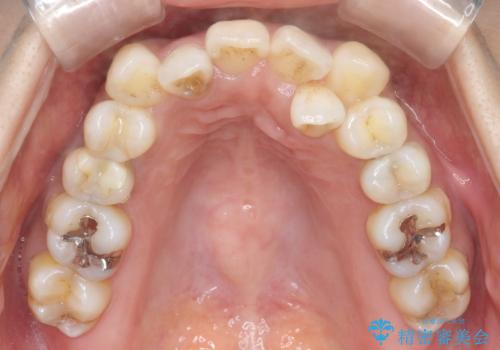

- 治療計画

- 治療中は歯磨きがしにくくなるため、虫歯や歯周病になりやすくなります